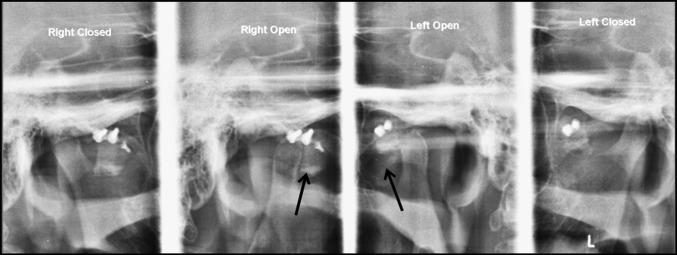

Intra-operatively condylar movements are checked for adequate restriction especially on medial aspect. Postoperatively soft diet is advised and radiographs are obtained to evaluate the efficacy of the procedure (Fig. 4).

Fig. 4.

Postoperative radiograph showing graft (black arrow) restricting movement of condyle